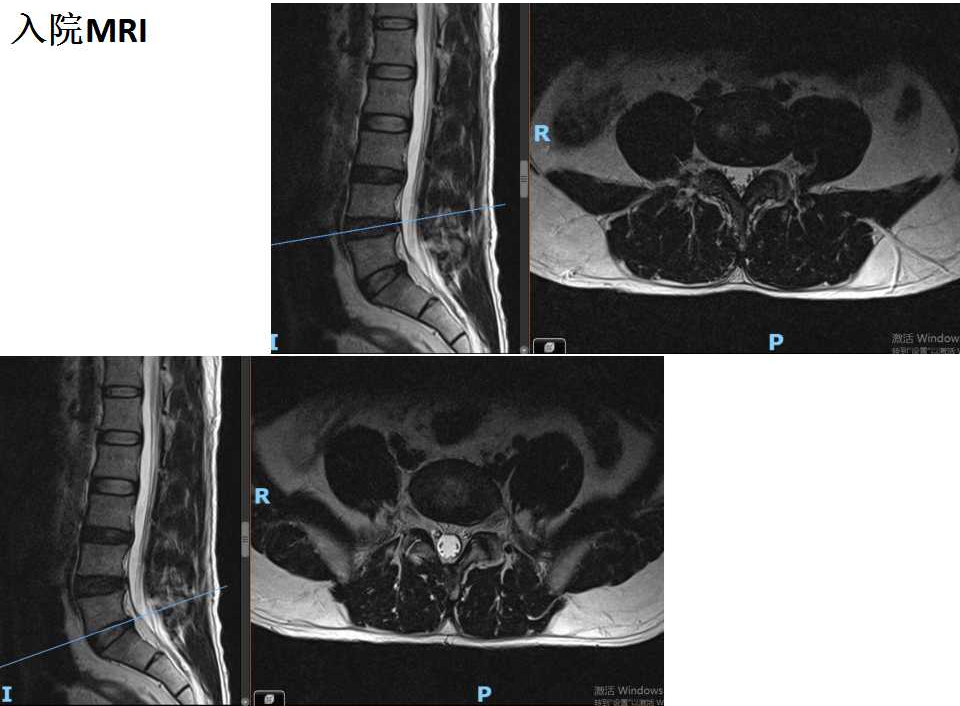

腰椎MRI未见椎间盘突出以及脊髓受压